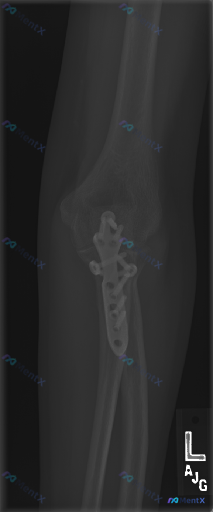

这份左肘术后X光报了“未见明显异常”,但真的没问题吗?

整理到一份左肘部的影像分析资料,先抛出来讨论一下。 这份是侧位X光片,基本情况是:尺骨近端有接骨板+多枚螺钉内固定,影像报了「内固定在位、骨皮质轮廓完整、关节对位好、无明显脂肪垫征」,结论倾向于「术后改变,未见明显异常」。 但结合临床背景来看,这张片子背后其实藏着几个高风险的「异常方向」——尤其是如...